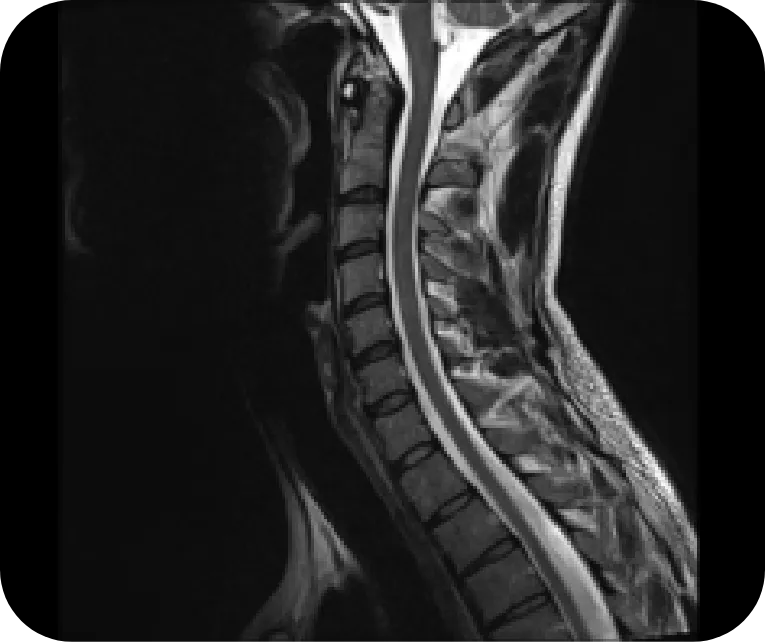

Cervical Spine

NMOSD

Longitudinally extensive transverse myelitis, characteristic of NMOSD, extending into the area postrema

Reprinted with permission from Radiographics, 2018;38(1):169-193. ©RSNA

MS

Ovoid and longitudinally short lesions typical of MS myelitis